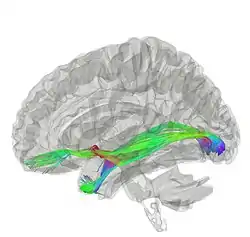

![]() Tractography of anterior commissure | |